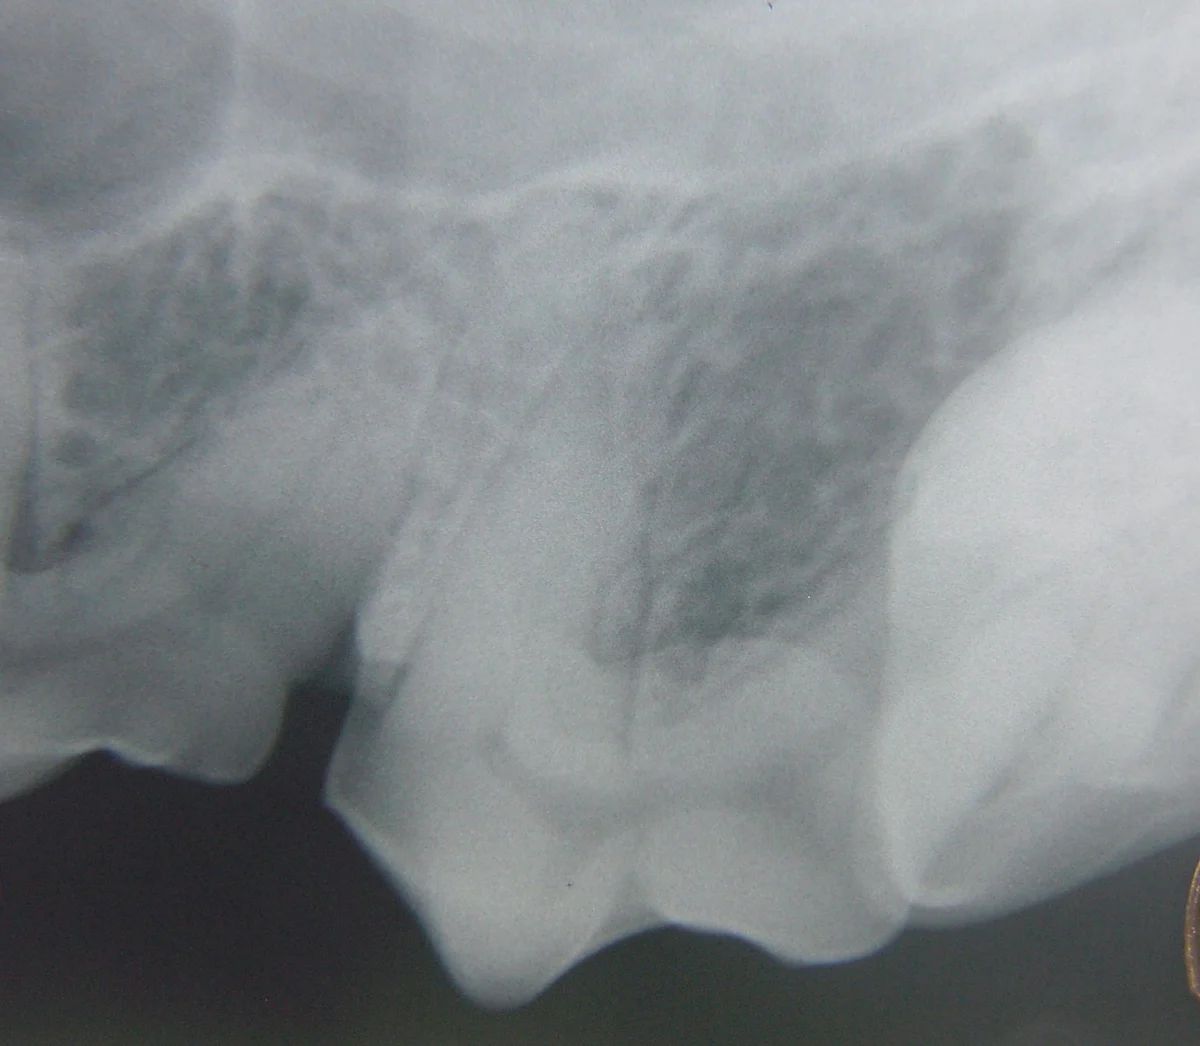

A suborbital swelling or draining tract as seen in this patient would be a good indication for dental radiographs of the maxillary 4th premolar tooth and adjacent teeth.

Suborbital swellings: Look for root tip infection or cystic teeth

Proper positioning of the x-ray machine tubehead (A). Again, it is not directed perpendicular to the long axis of the tooth or perpendicular to the plane of the film, but is instead placed halfway between these two reference alignments (B). This creates a good diagnostic image of the maxillary 4th premolar crown, roots, alveolar bone, and apexes of the roots (C). One limitation is the superimposition of the mesial roots on each other. The clinical significance of this superimposition is arguable.

For example, if periodontal bone loss is noted around one of the roots, periodontal probing should help to determine which root is involved. If periapical osteolysis is noted, then endodontic disease, which would affect all roots, is probably present. There may be instances where using radiographic techniques to separate the mesial roots may be helpful. If one of the roots were undergoing root resorption or ankylosis, this information may be valuable before extraction. Determination of the individual roots is also helpful when navigating the canals during initial assessment for root canal therapy or determination of root canal length.